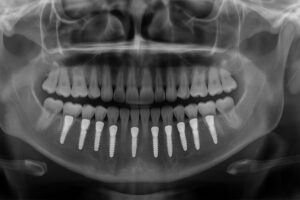

One of the most common metals used in dental implants is titanium, renowned for its strength and biocompatibility. It’s favored due to its ability to fuse with bone over time, leading to successful and stable long-term results. Titanium alloys provide added benefits, offering enhanced durability and a reduced risk of fracture. Alternatives such as zirconia represent a growing interest, particularly for those prioritizing metal-free options. This ceramic material, while distinct in composition, offers similar stability and is valued for its aesthetic appeal. The selection amongst these materials largely depends on individual needs and specific health considerations.

The choice of metal in implants is a major determinant in their lifespan and overall success. Correct metal selection promotes effective integration with the bone, enhancing the implant’s durability and capacity to handle daily wear. For most patients, titanium has served as a gold standard, offering reliable success rates and minimal complications. Its properties ensure that the structural integrity of the implant remains uncompromised over extensive periods. On the other side, advances in ceramics like zirconia continue to offer valuable alternatives with promising results. Each type of material ensures a versatile approach to meeting varied patient needs and expectations.